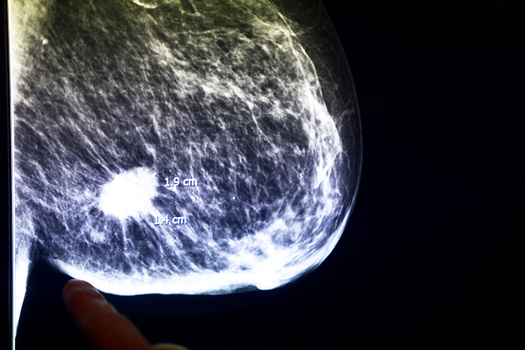

Выйдя из кабинета врача с онкологическим диагнозом, человек остается наедине со страхом и бесконечными направлениями на анализы. Зато потом, уже после победы над раком, люди с таким опытом могут помочь другим. Став равным консультантом, можно поддерживать новичков психологически, составить план действий, объяснить рекомендации врача или просто подсказать, где лучше выбрать парик после химиотерапии. Для женщин, которые столкнулись с диагнозом «рак молочной железы», такая поддержка особенно важна: часто им приходится привыкать жить без части своего тела. И опыт тех, уже прошел через это, для них очень ценен. О том, как в России работают равные консультанты в онкологии, рассказала руководитель направления обучения и оценки программы «Женское здоровье» Татьяна Голованова.

В случае с женской онкологией речь может идти еще и об ампутации органа, связанного с репродуктивным здоровьем. И это всегда очень тяжело для женщины психологически, страдает самооценка. Реабилитация нужна каждой пациентке. Не бывает так, чтобы человек реабилитировался просто сам по себе. От женщины ждут, что ее вылечат, она встанет и, весело помахивая единственной своей грудью, пойдет дальше жить как жила. У нас просто не говорят о том, что нужны реабилитация и сопровождение.